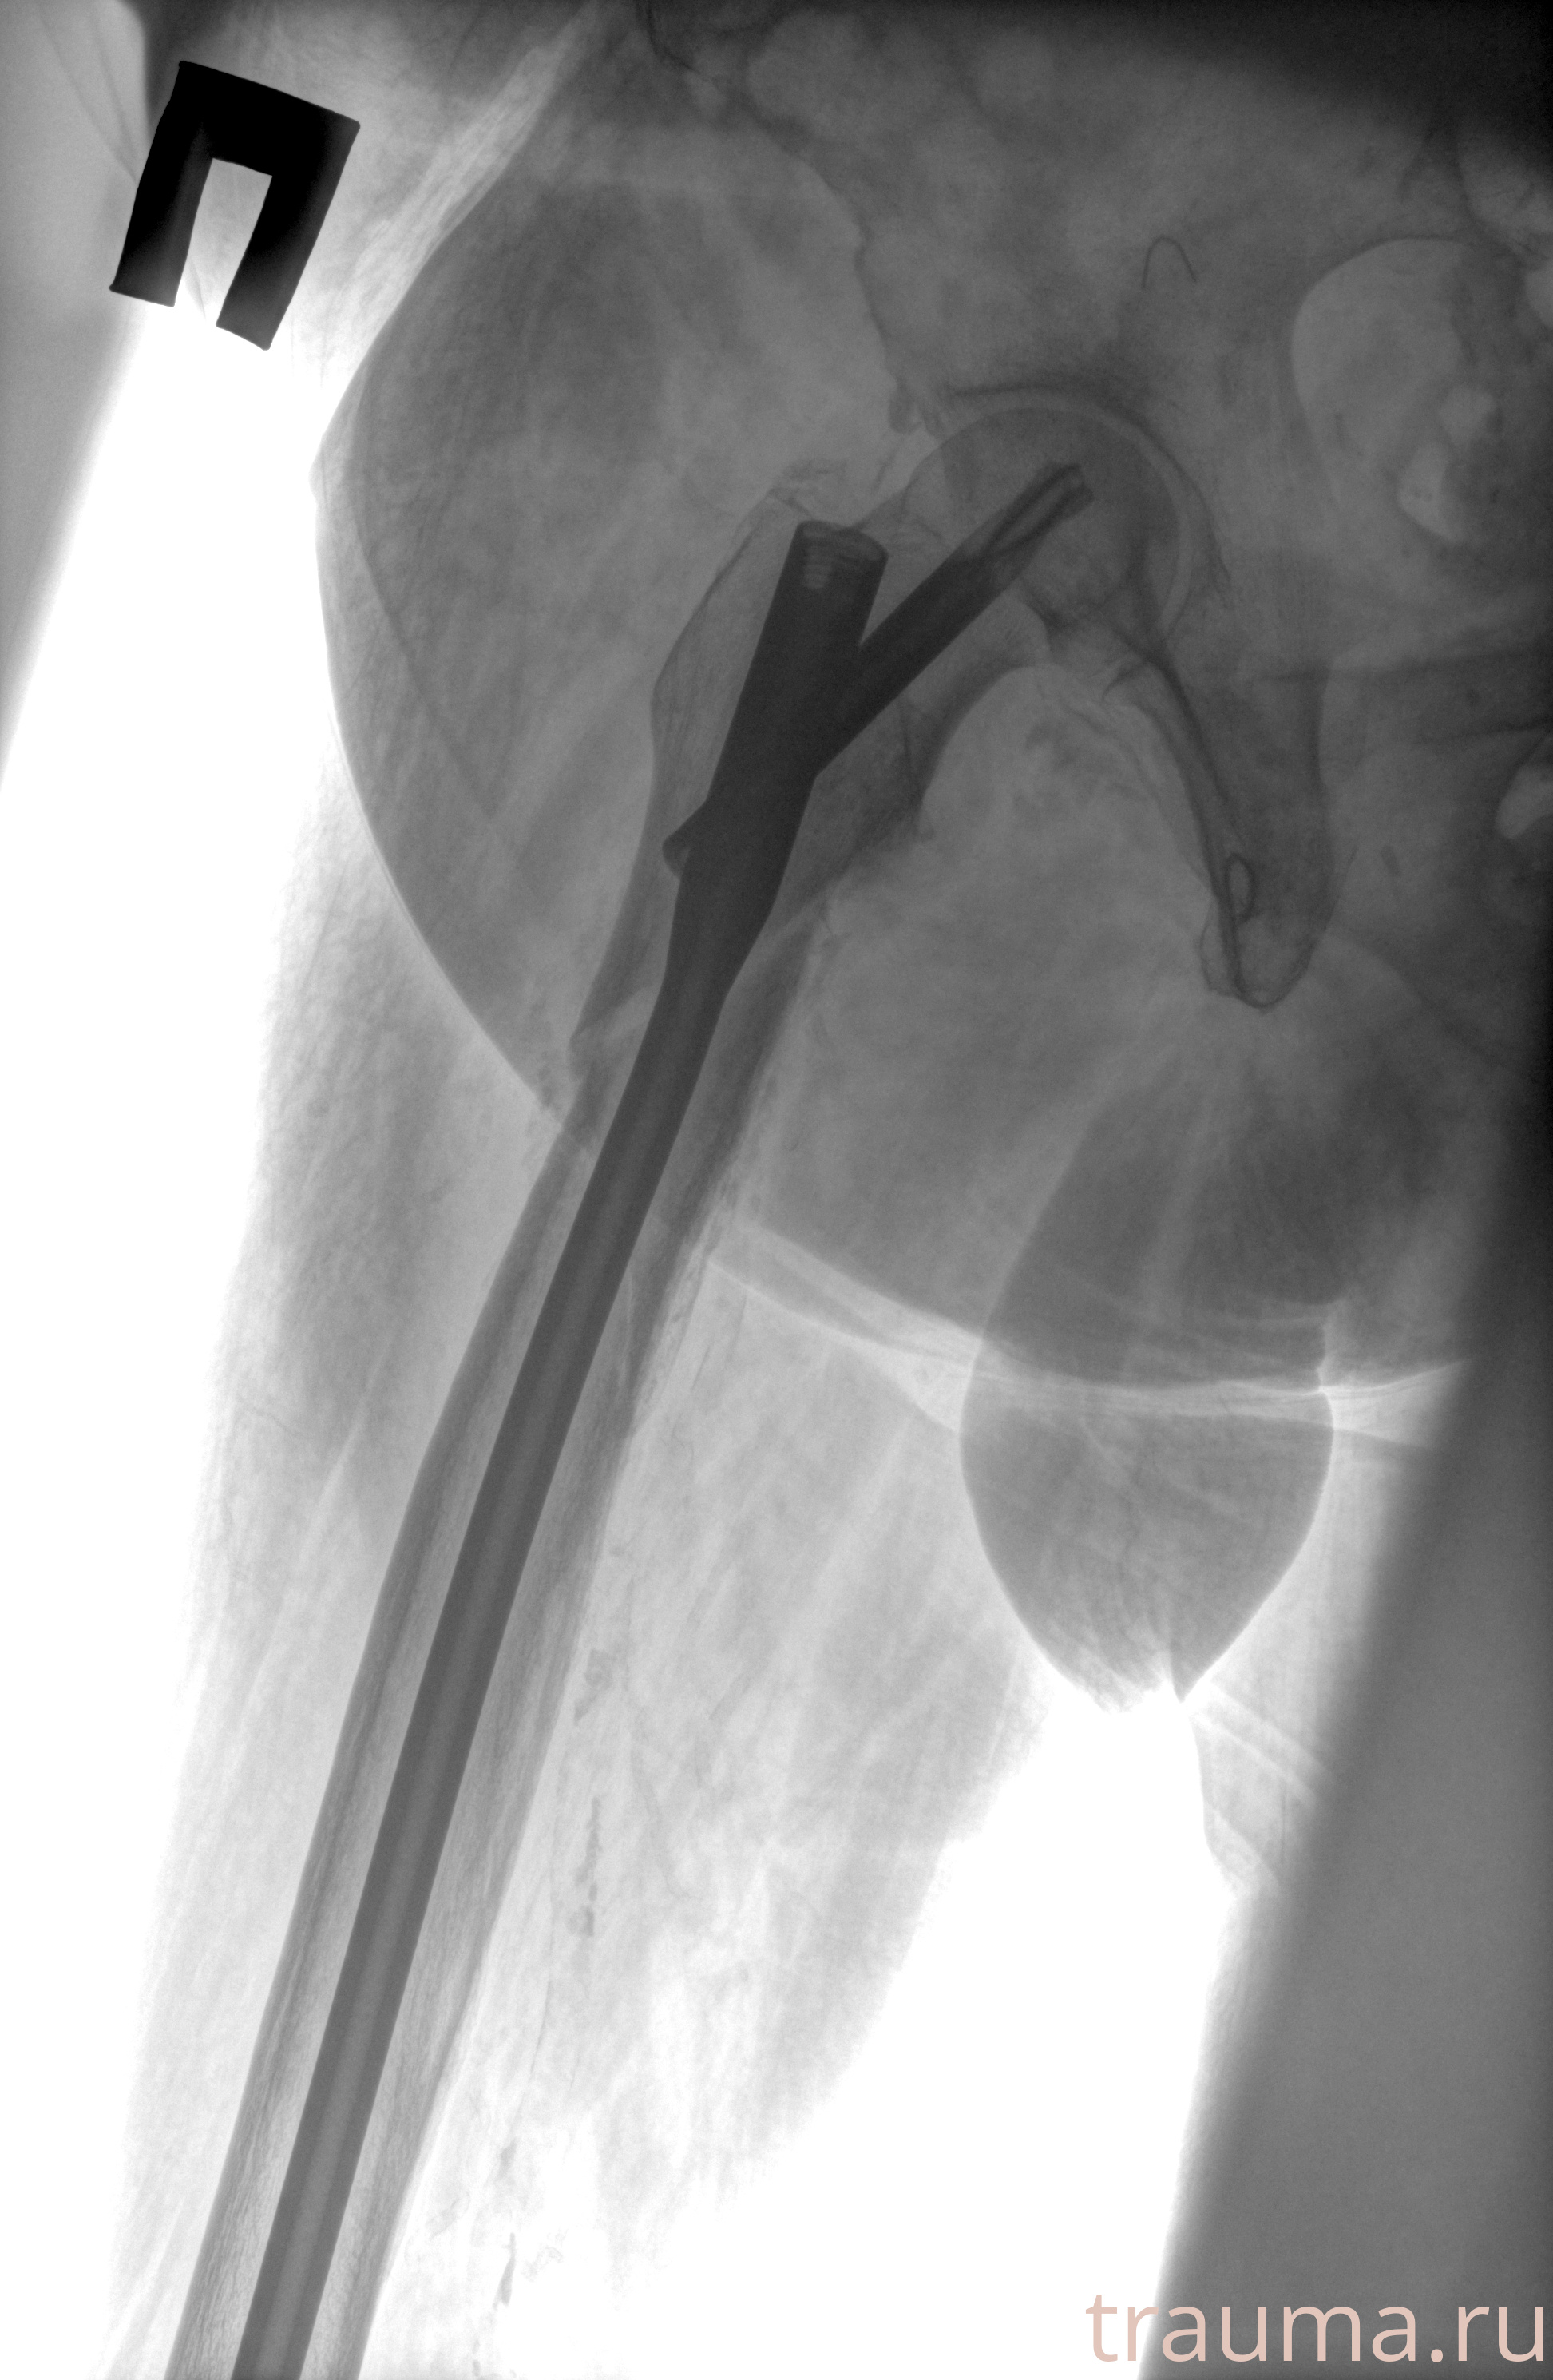

Рентгенограммы

Рентген на дому: по вашему адресу приезжает врач-рентгенолог, травматолог-ортопед с мобильным рентгеновским аппаратом, проводит диагностику травмы или заболевания, делает необходимые рентгенограммы, дает рекомендации по дальнейшему лечению. Получить качественные снимки в домашних условиях возможно благодаря уникальной методике, разработанной МосРентген Центром для института  Склифосовского